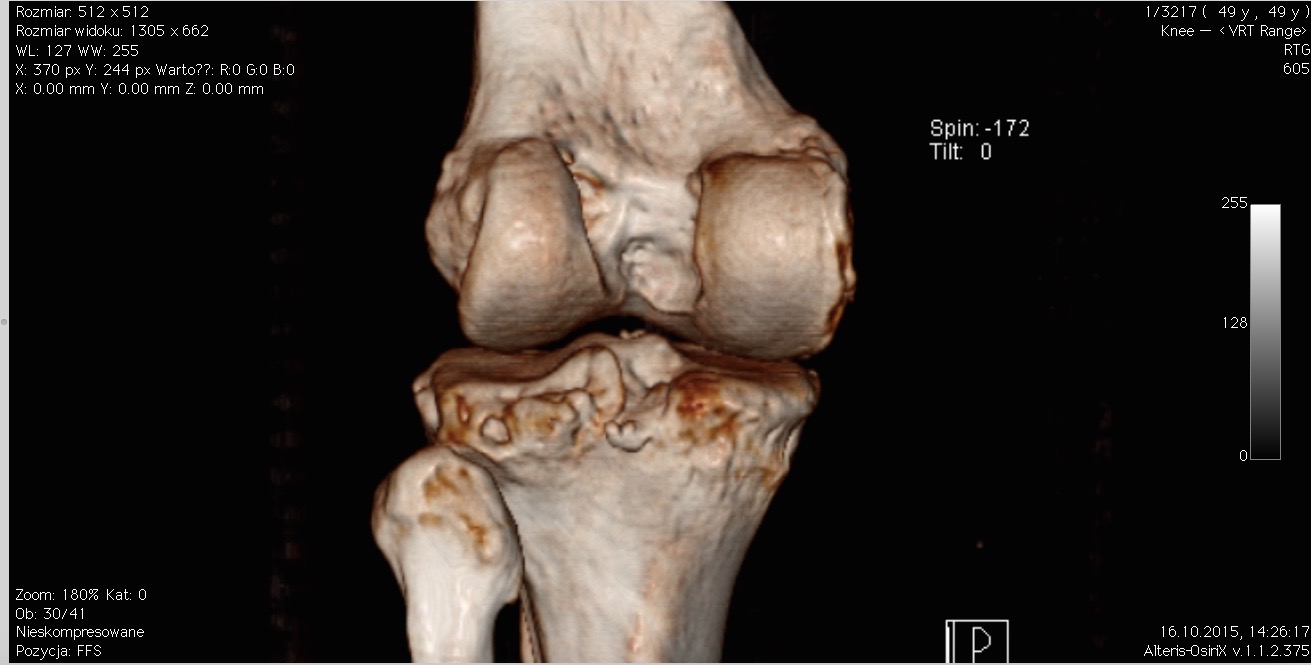

Czasem jednak wykonanie TK jest niezbędne. Jego wielkim atutem jest między innymi możliwość podania kontrastu, czyli środka, który podczas badania daje możliwość precyzyjnego określenia miejsca urazu czy ujawnia dodatkowe, niezauważalne na pierwszy rzut oka patologie. Tomograf komputerowy w schorzeniach ortopedycznych znakomicie sprawdza się na przykład przy podejrzeniu złamania zmęczeniowego kości piszczelowej i innych, nie łatwych do diagnostyki uszkodzeń kostnych. Nierzadko stosuje się go także w różnicowaniu chorób na tle nowotworowym. Przydatną możliwością TK jest również obrazowanie poszczególnych elementów kostnych w technologii 3D.

Obraz stawu kolanowego (od tyłu) wykonany tomografem komputerowym w technologii 3D.